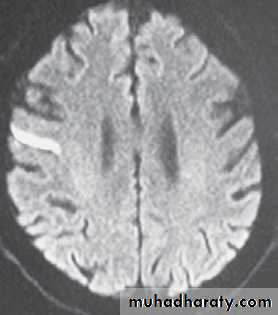

A CT scan of the brain should be obtained

before the start of treatment and examined forhemorrhage or early ischemic changes. If a focal

area of low density is seen that involves more

than one third of the middle-cerebral-artery territory,most treatment protocols recommend withholding thrombolytic therapy, because in some

studies this finding (which suggests irreversible

injury) has been predictive of subsequent hemorrhagic transformation of the infarct.